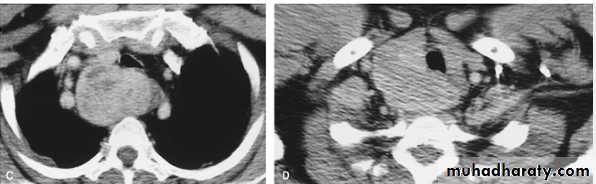

Subpulmonary pleural effusion. On the (A) erect PA and (B) lateral radiograph the effusion simulates a high hemidiaphragm. (C) Ultrasound and (D) CT clearly show that the effusion is located above the diaphragm. Arrows = diaphragmatic area.